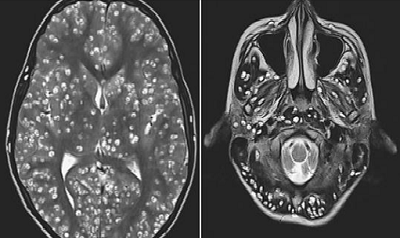

An MRI brain scan revealed the patient had cysts throughout his brain, with the damage being consistent with the life-threatening condition neurocysticercosis.

An MRI scan showed the patient had numerous cysts in his cerebral cortex - the outermost layer of the brain, which is responsible for thinking and processing information collected via our five senses.

Lesions were also in his brain stem, which is at the base of the vital

And cysts were found in his cerebellum - the area at the back of the brain that coordinates voluntary movements, like posture, speech and coordination.

Doctors noted the extent of the man's brain damage was consistent with that of neurocysticercosis.